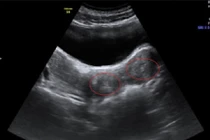

| Em bé chỉ mới 3 tuần tuổi nhưng trông nhăn nheo như bà lão. |